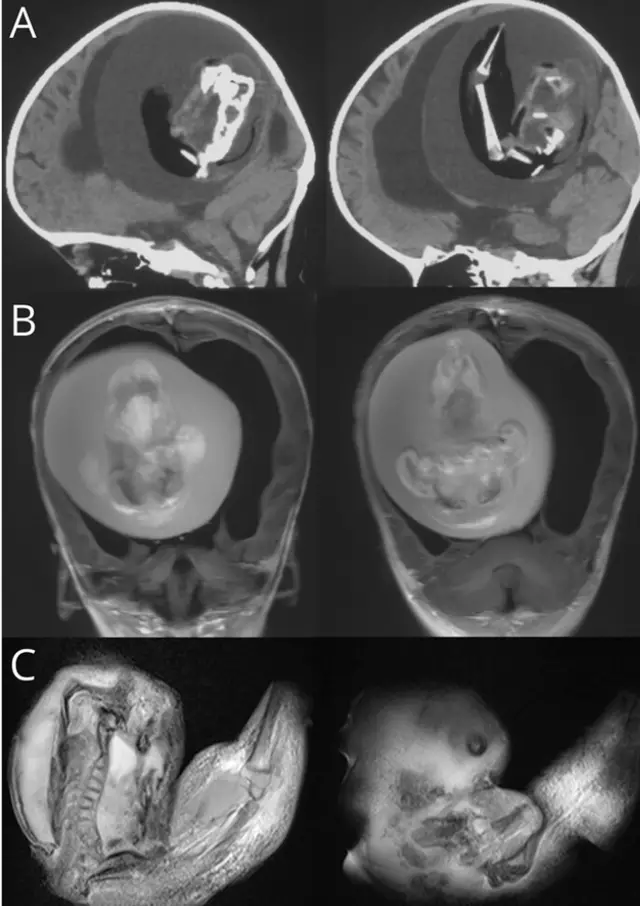

The turning point came when doctors performed a CT scan. They found a large mass inside her brain with bone-like features and a clear outline. To their shock, it was a malformed fetus — a rare condition known as a parasitic twin.

This rare disorder happens when one twin stops developing and becomes trapped inside the other. It occurs in only one out of every half-million births. The mass pressed against the areas of the brain responsible for movement, learning, and speech.

Doctors knew they had to act quickly. They performed a craniotomy to remove the mass, hoping to relieve the pressure and give the little girl a chance. Inside, they could see faint shapes of a tiny mouth, eyes, and arms.